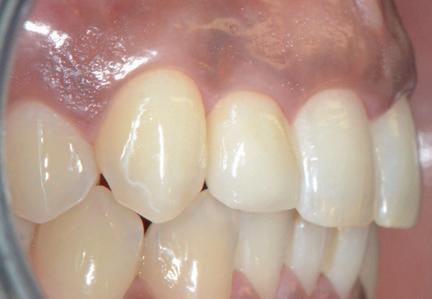

Situation avant la prise d’empreinte en sept. 2009

• Etude de la prothèse sur implants (provisoire, immédiate et définitive).

Situation pré-opératoire 09/2018 09/2018

Contrôle à 10 ans en septembre 2018.